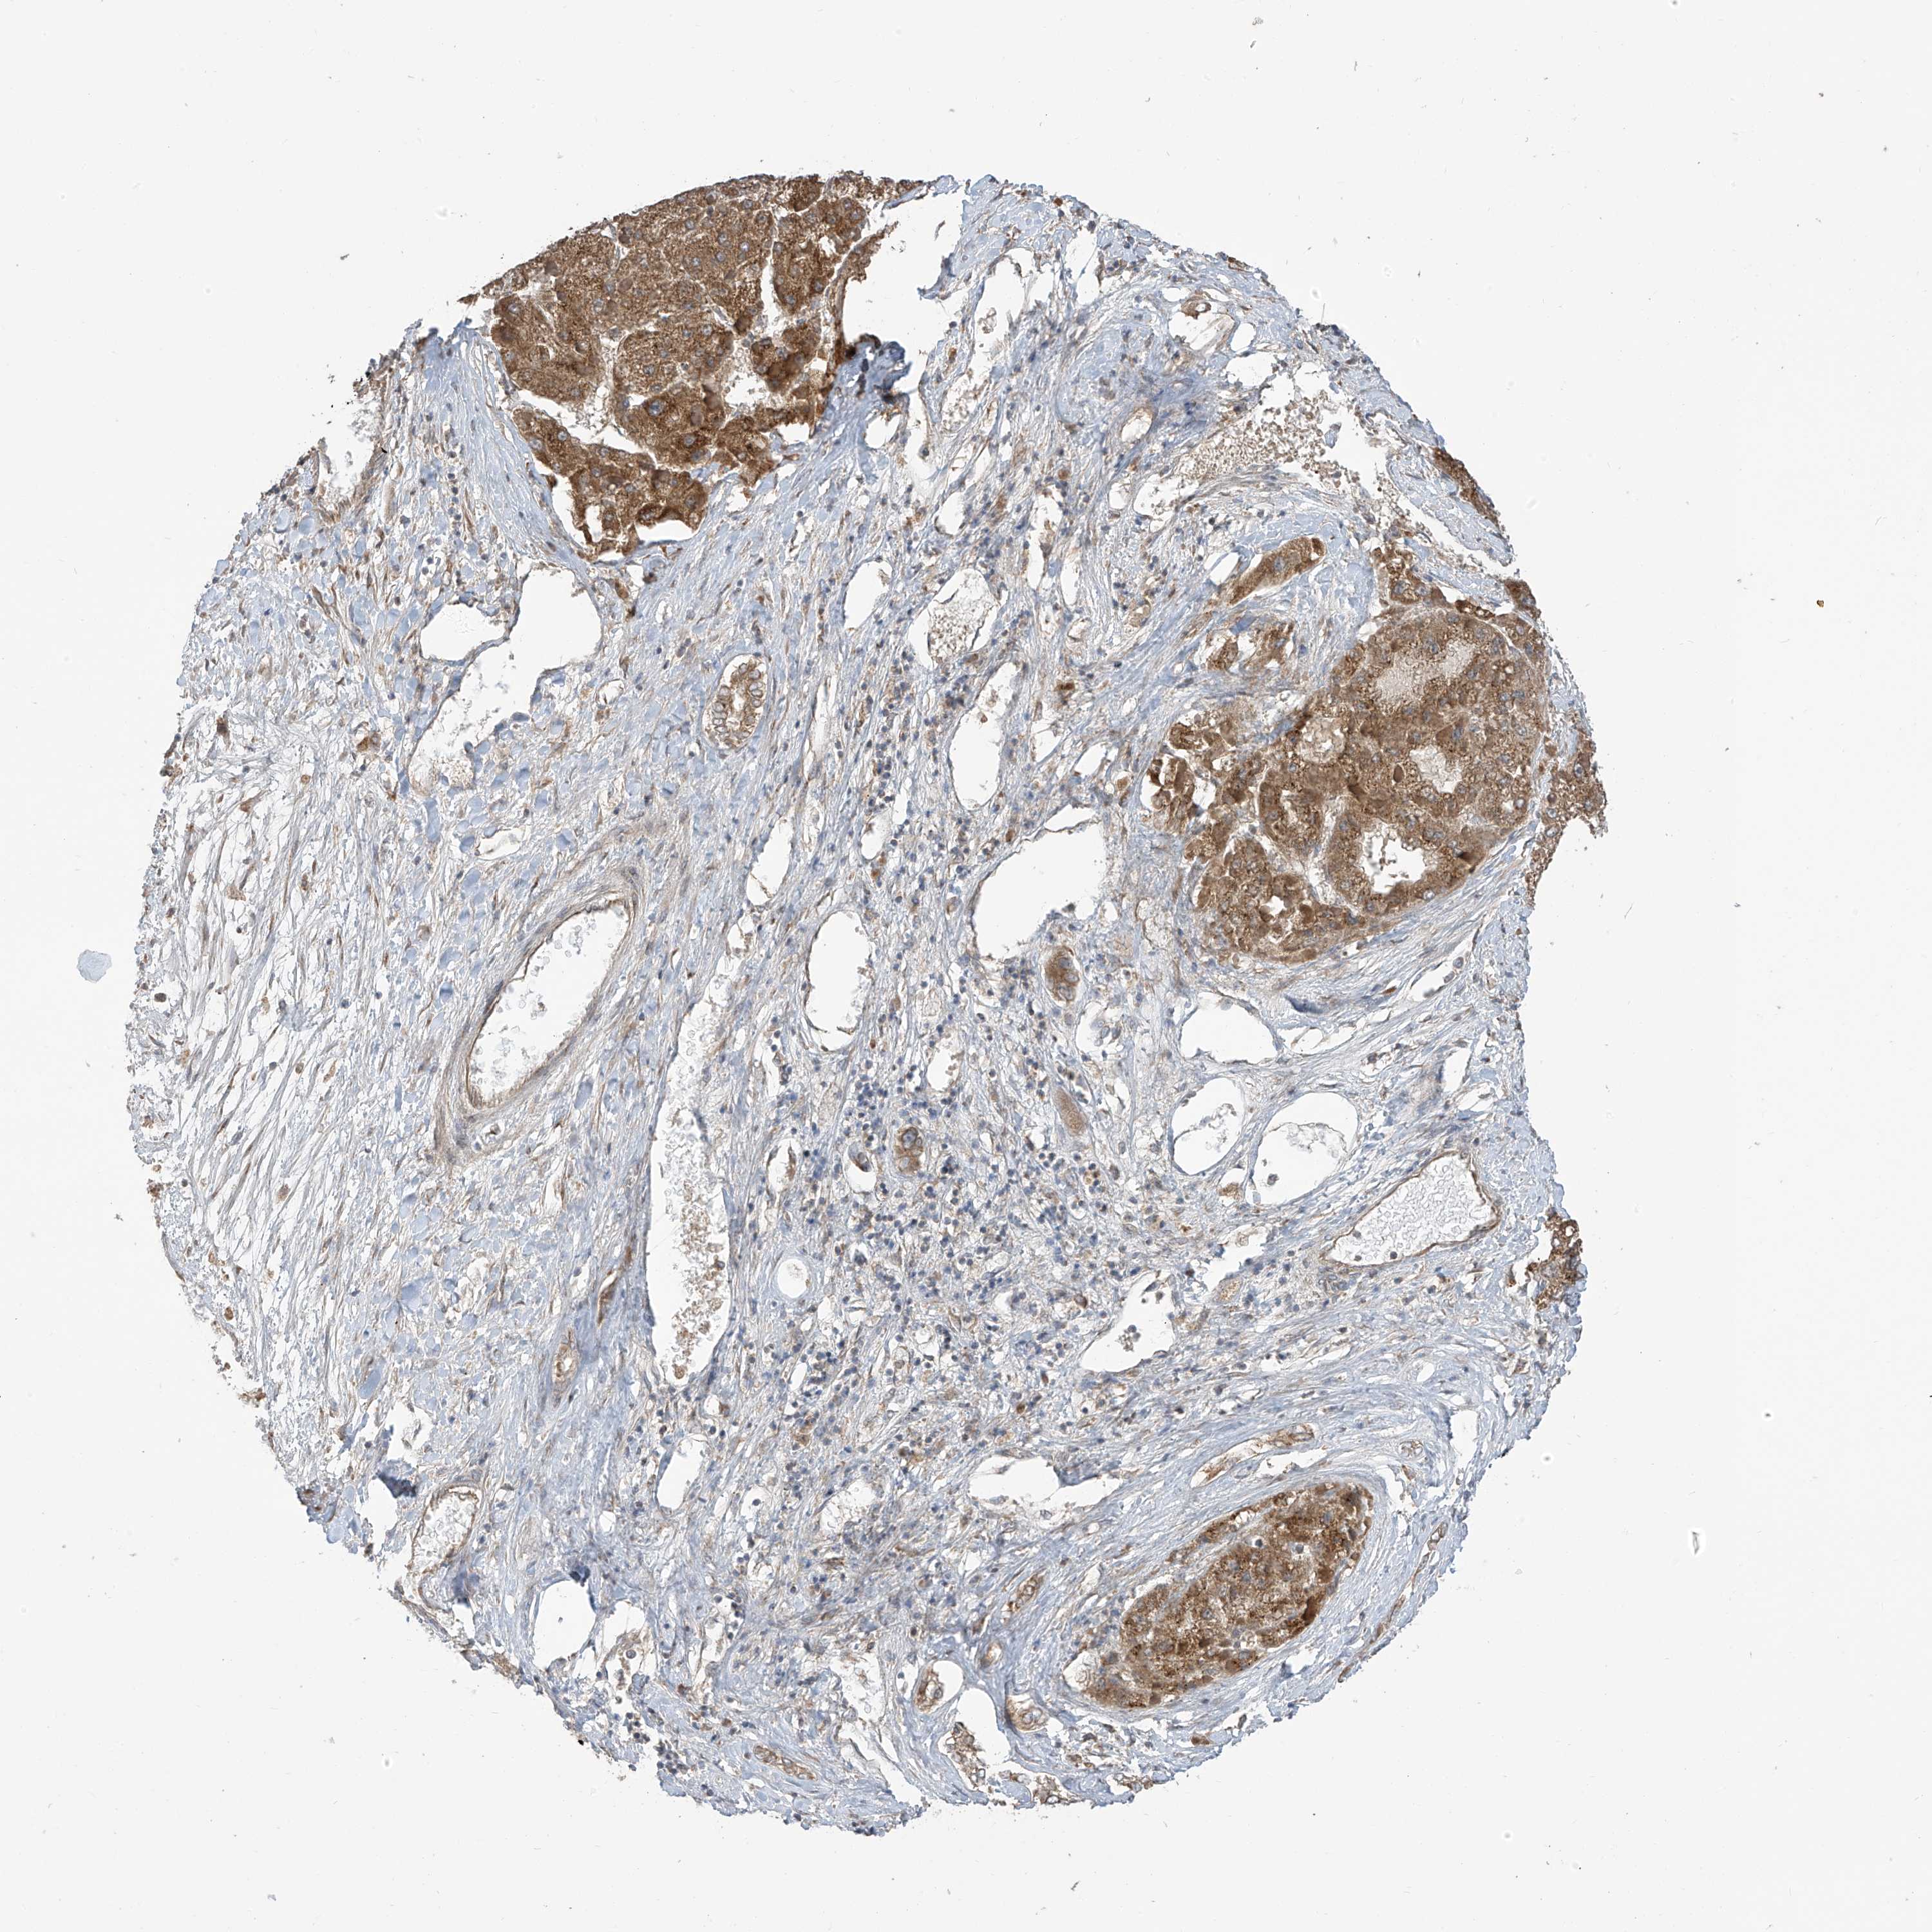

LIVER CANCER - Protein expressioni

A mouse-over function shows sample information and annotation data. Click on an image to view it in a full screen mode. Samples can be filtered based on level of antibody staining by selecting one or several of the following categories: high, medium, low and not detected. The assay and annotation is described here.

Note that samples used for immunohistochemistry by the Human Protein Atlas do not correspond to samples in the TCGA dataset.

Antibody stainingi

Antibody staining in the annotated cell types in the current human tissue is reported as not detected, low, medium, or high, based on conventional immunohistochemistry profiling in selected tissues. This score is based on the combination of the staining intensity and fraction of stained cells.

Each image is clickable and will lead to virtual microscopy that enables deeper exploration of all samples and also displays staining intensity scores, fraction scores and subcellular localization as well as patient and tissue information for each sample.

Antibody HPA034602

Antibody HPA034603

Antibody CAB033424

Staining

High

Medium

Low

Not detected

Intensity

Strong

Moderate

Weak

Negative

Quantity

>75%

75%-25%

<25%

None

Location

Nuclear

Cytoplasmic/membranous

Cytoplasmic/membranous,nuclear

Cholangiocarcinoma

Carcinoma, Hepatocellular, NOS